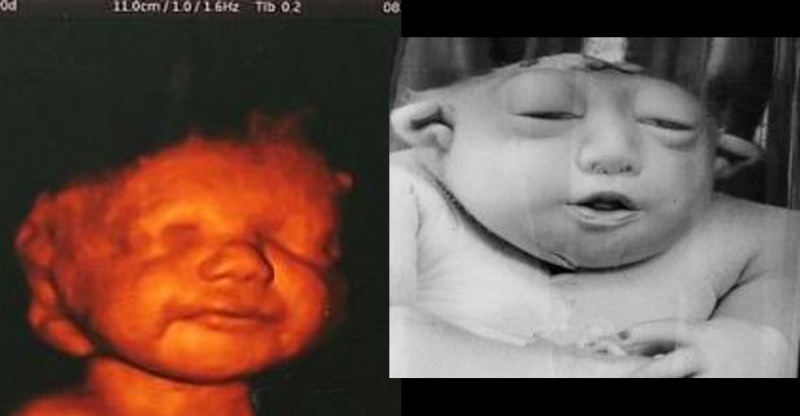

2、敏感期(胚胎期):末次月经后29天~70天,即妊娠3-8周。这个时期属胎儿器官分化时期,如中枢神经系统(脑)、循环系统(心脏)、感觉系统(眼、耳)、肌肉骨骼系统(四肢)等。在这个时期,胚胎对药物最敏感,易发生严重畸形。

无脑儿